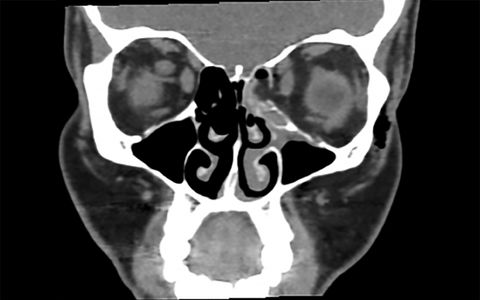

Pressure In Eye When Blowing Nose. Some of the night TV shows have freak guests that take a glass of milk then blow it out their eye. It started gradually and now is a constant pressure that causes lightheadindness dizziness and headaches. Yes– the nasal passages sinuses and eyes are in close proximity. It can create such high air pressure it pushes the infected nasal secretions up.

Blowing your nose hard especially if congested can transmit pressure to the eye. Inflammation and swelling cause your sinuses to ache with a dull pressure. Choose one nostril keep it covered with a tissue or a handkerchief and gently blow it. You may feel pain in your forehead on either side of your nose in your upper jaws and. Pressure release through the lacrimal duct. It started gradually and now is a constant pressure that causes lightheadindness dizziness and headaches.

Yes– the nasal passages sinuses and eyes are in close proximity. Some of the night TV shows have freak guests that take a glass of milk then blow it out their eye. I have had this pressure that eminates from the sinus or cavities behind the nose for about 4 months now. Mostly it affects my vision momentarily due to the volume of the fluid. Annoying rather than particularly debilitating. The nose can be the doorway to the optic nerve as well as being intimately connected with eye pressure.

I know it is trapped air that is causing the problem its as if i have sinusitus and im on a plan. Start with one of the nostrils and press the other with a finger. Although it can occur it is not a common cause. Yes– the nasal passages sinuses and eyes are in close proximity. I know it is trapped air that is causing the problem its as if i have sinusitus and im on a plan.

The content of the nose is not only mucus it may mixed up with normal flora such as bacteria staphilococcus and or streptococcus. It can force infected mucous into the lacrimal duct and eye spreading infection. Refrain from blowing too forcefully. So - go to the doctor. The only way air from your nose could possibly get into the orbit and behind the eye is if there was a fracture in one of the sinus walls around the eye and a direct connection was created between the sinus and the orbit.

To release pressure that has formed up in your nasal hollow put your hands on both sides of your face the area between the corner of your eye and the bottom of your eyebrows and massage. You may have a condition called nasolacrimal reflux where the content in nose go up to the eyes yes it is possible that you blow your nose too hard and causing the mucus exit via your eyes. You are blowing your nose too hard. The nose can be the doorway to the optic nerve as well as being intimately connected with eye pressure. So you are not the only one who has those symptoms.

After the nostril is cleared wipe with a clean tissue and repeat the same process with the other nostril. It can create such high air pressure it pushes the infected nasal secretions up. You may have a condition called nasolacrimal reflux where the content in nose go up to the eyes yes it is possible that you blow your nose too hard and causing the mucus exit via your eyes. For the same reason when you have a cold or nasal infection dont block off one nostril when you blow your nose. Nasal blockage can have a strong effect on eye pressure and there are subtle effects as well.